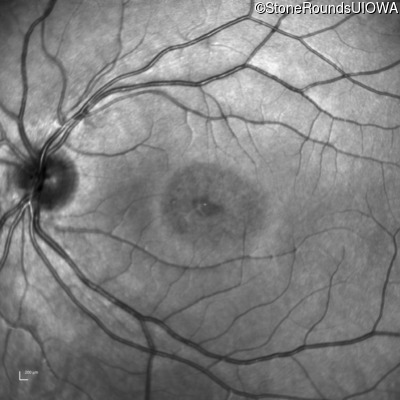

AR Stargardt Disease (IIA)

Age at visit: 18 years

This 18 year old woman first noticed some difficulty seeing the blackboard when she was 15 years old.

AR Stargardt Disease ABCA4 Arg1108Cys CGC>TGC Val2114Val GTG>GTA AR